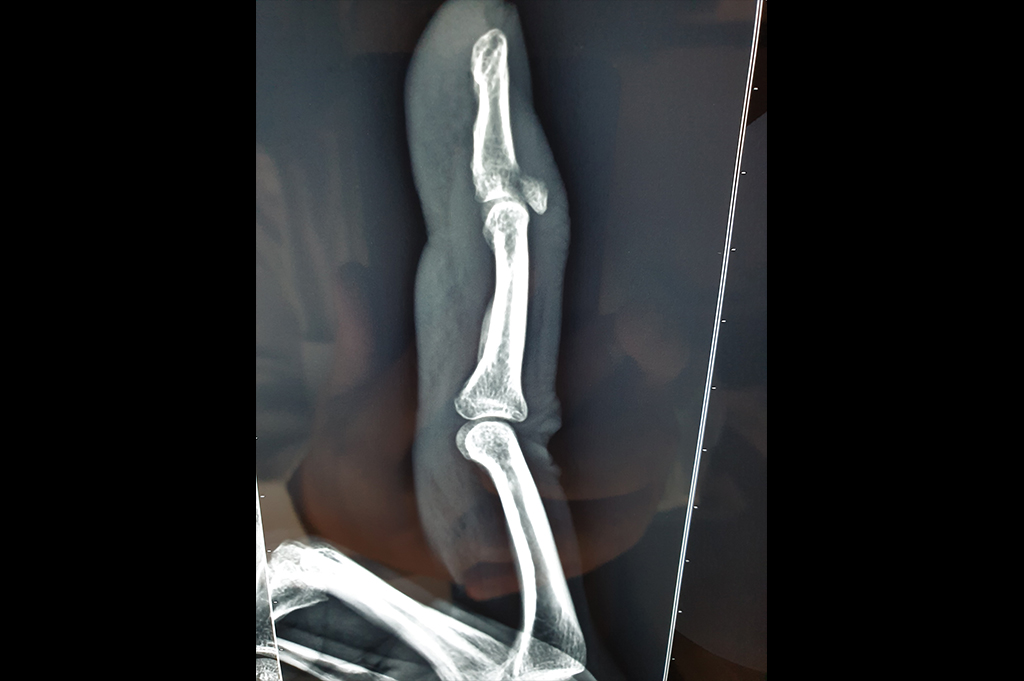

Mallet Finger